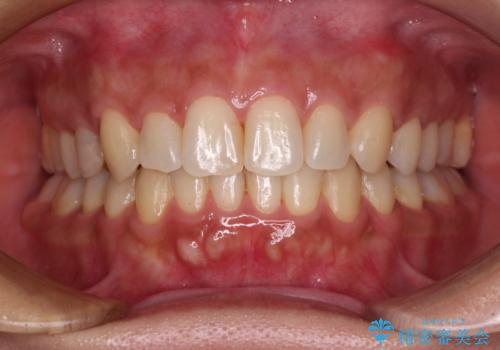

- 患者様

- 30代女性

- 矯正装置

- インビザライン

- 費用(概算)

- 治療費の目安: 85万円(税込)費用は治療当時の料金となります